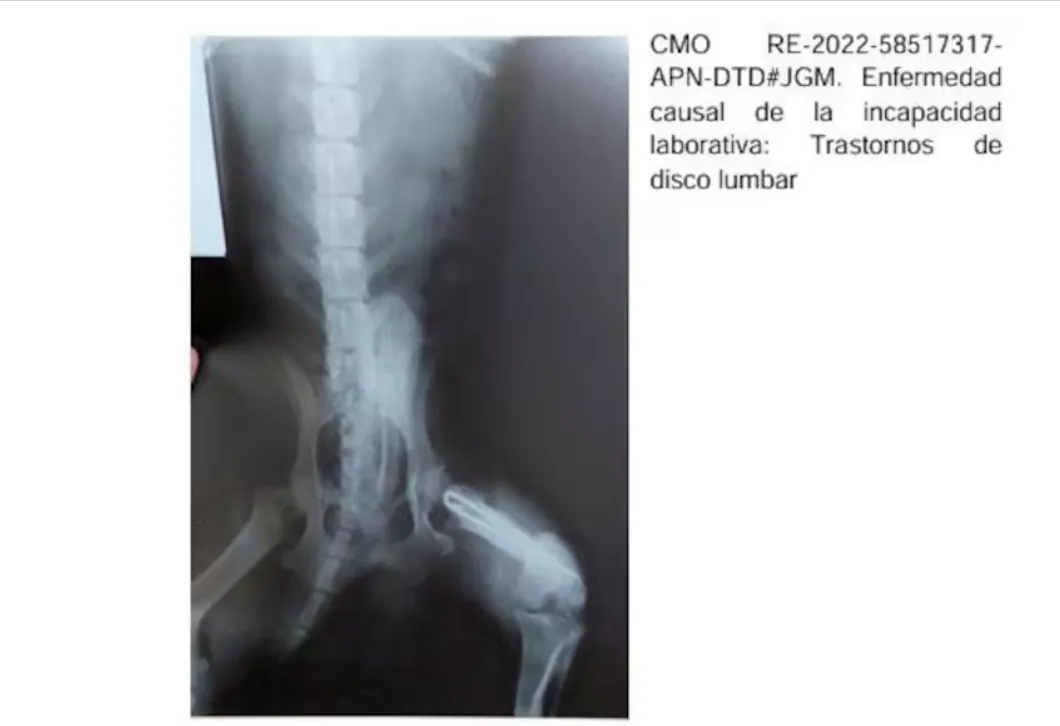

En la muestra auditada de más de 2500 pensiones, la agencia anuló las que habían sido otorgadas irregularmente; incluían expedientes en los que la radiografía de un perro acompañaba el certificado médico por un trastorno de disco lumbar emitido por un médico de Corrientes. En Chaco, con la misma radiografía de hombro se justificaron 150 pensiones por invalidez.